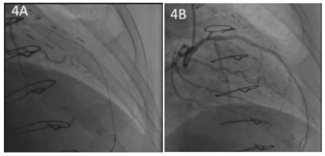

A 60-year-old female underwent a left ventricular assist device (LVAD) implant during which a 1-mm Gore-Tex sheet (Gore Medical) was used to cover the device and outflow graft to prevent future sternal re-entry injury. Seven years later, she...